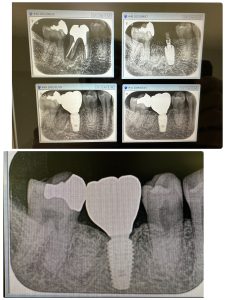

不良肉芽が凄かった方

プラットフォームスイッチングのお陰

皮質骨がシャープになっている 安定